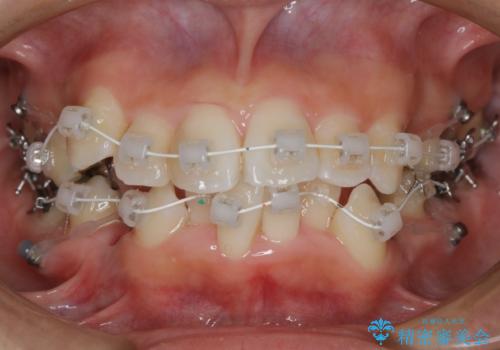

- ワイヤー審美装置

- 歯のガタつきと出っ歯が気になるので矯正治療を希望し来院された患者様です。

上下顎とも歯を並べられるスペースが無く、口元を下げたいというご希望だったので、抜歯とワイヤー矯正を併用した治療を計画しました。

抜歯スペースを利用し口元を大きく下げることが出来ました。